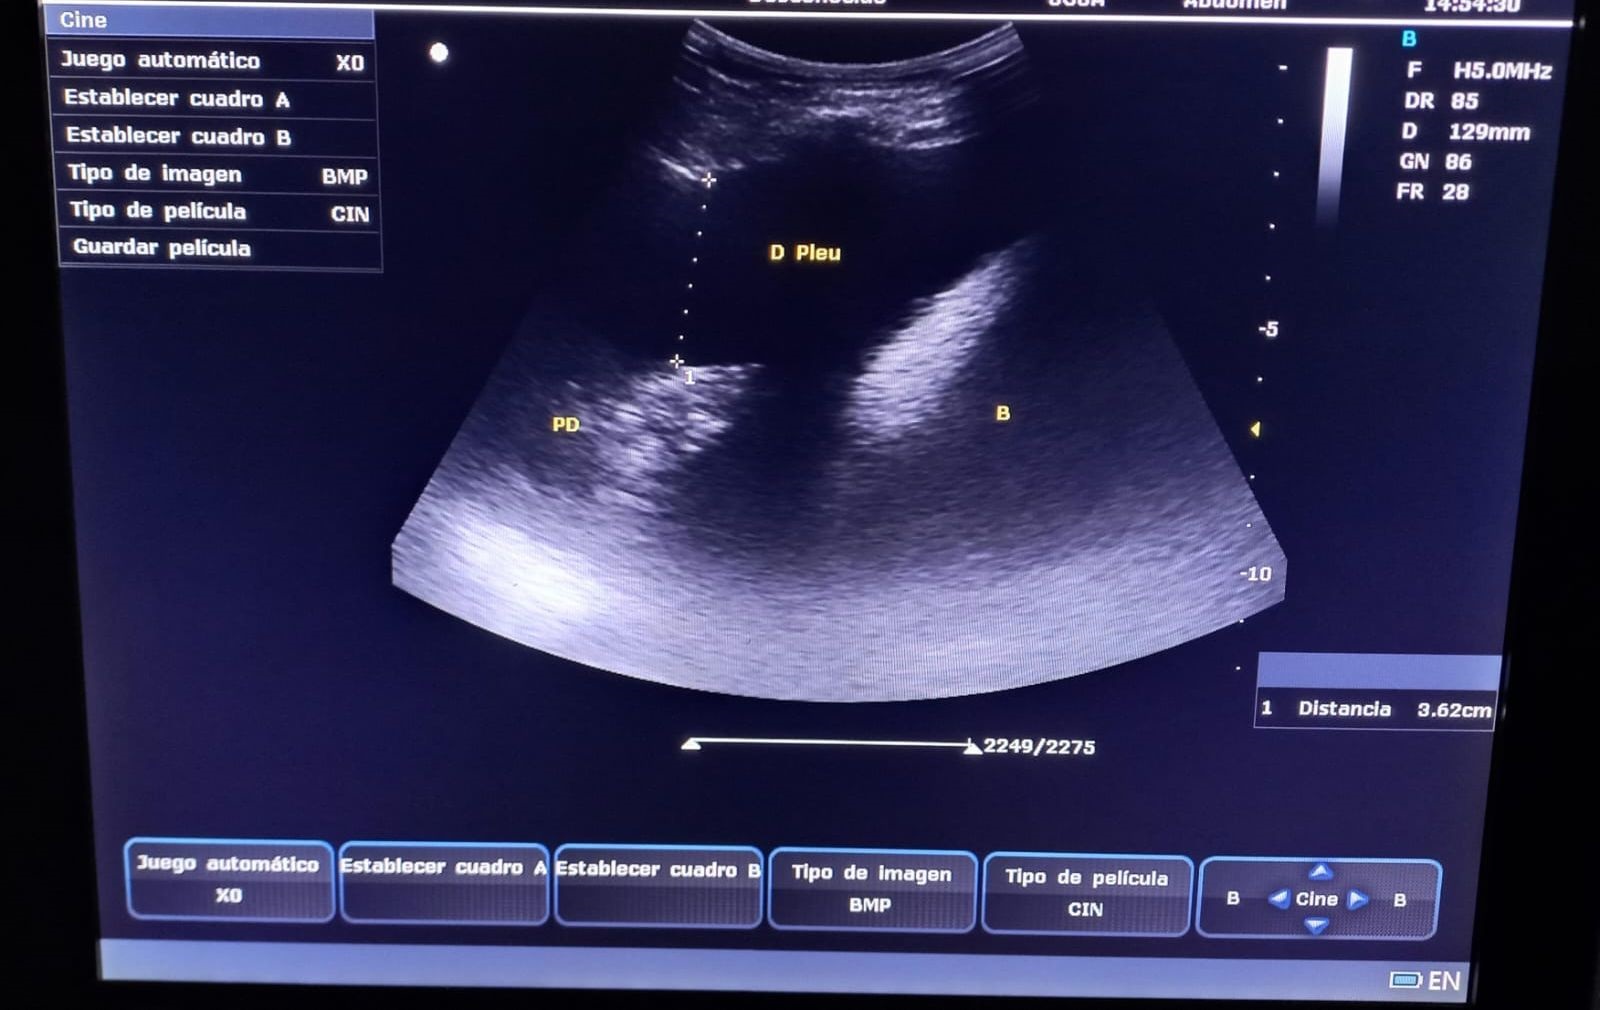

Desde 2022, tras la incorporación de un ecógrafo portátil en nuestro servicio, iniciamos formación específica en ecografía pulmonar, lo que permitió valorar el grado de congestión y la presencia de derrame pleural (DP) en pacientes con insuficiencia cardíaca congestiva (ICC), así como condensaciones pulmonares en casos de neumonía. En 2024, cursamos un Máster en ecografía clínica para atención primaria, incorporando el protocolo VEXUS para evaluar la congestión venosa sistémica. En 2025, completamos dos cursos semipresenciales que consolidaron esta práctica. La ecografía se integró en las visitas domiciliarias, optimizando tratamientos deplectivos y permitiendo seguimiento sin necesidad de traslados hospitalarios. El análisis de su uso entre enero de 2024 y junio de 2025 evidenció su valor clínico y la necesidad de formación específica para el equipo médico de HAD-AI.